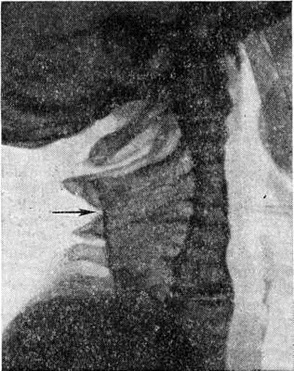

Диагностика заболевания основывается на клинические, симптомах с обязательным рентгенологическое обследованием шейного и верхнегрудного отделов позвоночника в задней и боковой проекциях. При очень короткой шее на рентгеновское изображение шейного отдела позвоночника в прямой задней проекции накладываются тени костей лицевого черепа и затылочной кости. В подобных случаях рентгенограмма, а тем более томограмма в боковой проекции (рисунок 1), как правило, выявляют все характерные детали и позволяют с уверенностью поставить правильный диагноз.

Основным рентгенологическое признаком Клиппеля — Фейля болезнь является деформация шейного, а иногда и верхнегрудного отдела позвоночника (рисунок 2), выражающаяся в слиянии нескольких тел позвонков, вследствие чего вертикальный размер шеи резко укорочен по сравнению с нормой. Наряду с этим может наблюдаться беспорядочное окостенение и слияние дуг позвонков и их отростков, а также незаращение дуг позвонков. Иногда костное слияние тел позвонков может быть неполным и между ними видны узкие полоски просветления, соответствующие недоразвитым хрящевым межпозвонковым дискам. При относительно редко наблюдаемых осложнениях Клиппеля — Фейля болезнь, связанных со сдавлением спинного и головного мозга, специальные методики рентгенологическое исследования — вертебральная ангиография (смотри полный свод знаний), миелография (смотри полный свод знаний) — позволяют выявить истинную причину и характер осложнения.